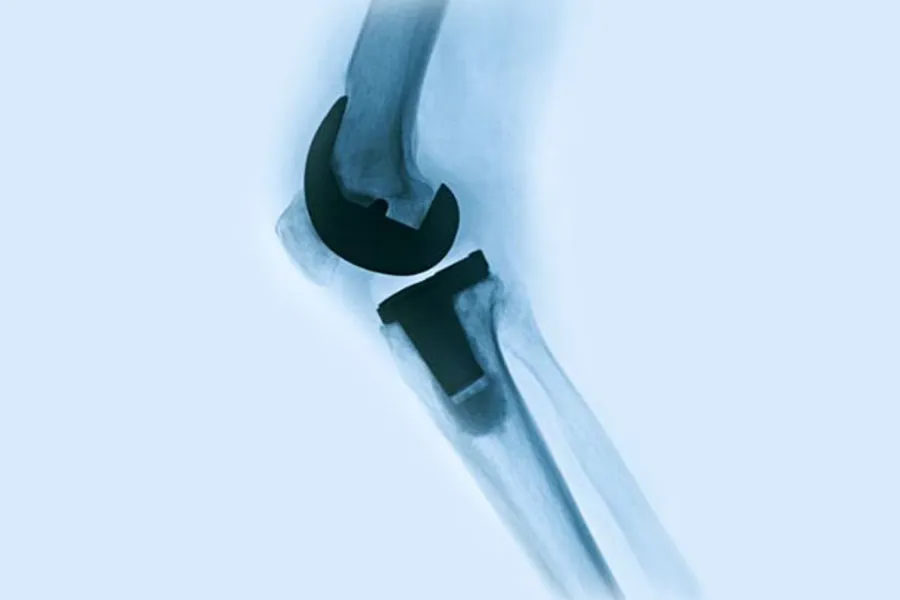

Antibiotic-Loaded Bone Cement & Arthroplasty (ALBA) er en stor randomisert registerstudie som skal undersøke effekten av antibiotika i sementen ved kneprotesekirurgi i Norge.

ALBA studien er en doubleblindet (pasienter og data analytikker), register basert multisenter randomisert kontrollert ikke-underlegenhetsstudie (non-inferiority). Pasienter som får sementert primær totalprotese i kne ved alle sykehus i Norge vil bli forsøkt inkludert og randomisert til antibiotika i beinsement (kontrollgruppe) eller beinsement uten antibiotika (eksperimentgruppe). Alle pasienter vil uansett få vanlig systemisk antibiotika profylakse under operasjonen etter nasjonale retningslinjer.